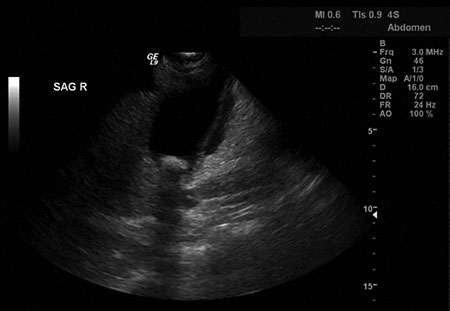

A 38-year-old woman is brought to the emergency department because of a 5-hour history of severe upper midabdominal pain, nausea, and vomiting. She rates the pain as an 8 on a 10-point scale. She has vomited three times since the onset of the pain; the vomit did not contain blood. She has had two similar episodes during the past 3 months but they were less severe and resolved without treatment. She has no history of serious illness. The patient does not use any medications. She drinks one glass of wine weekly but does not smoke cigarettes; she does not use any other substances. BMI is 25 kg/m2. Temperature is 38.7°C (101.7°F), pulse is 102/min, respirations are 16/min, and blood pressure is 136/84 mm Hg. Pulse oximetry on room air shows an oxygen saturation of 98%. The patient is lying down and appears to be in pain. Abdominal examination discloses tenderness to palpation over the epigastric region and right upper quadrant. The tenderness is more severe with palpation while the patient is breathing deeply. The remainder of the physical examination discloses no abnormalities. Results of laboratory studies are shown:

Abdominal ultrasonography is shown. After administering hydration with 0.9% saline and pain control with morphine sulfate, which of the following is the most appropriate next step in management?